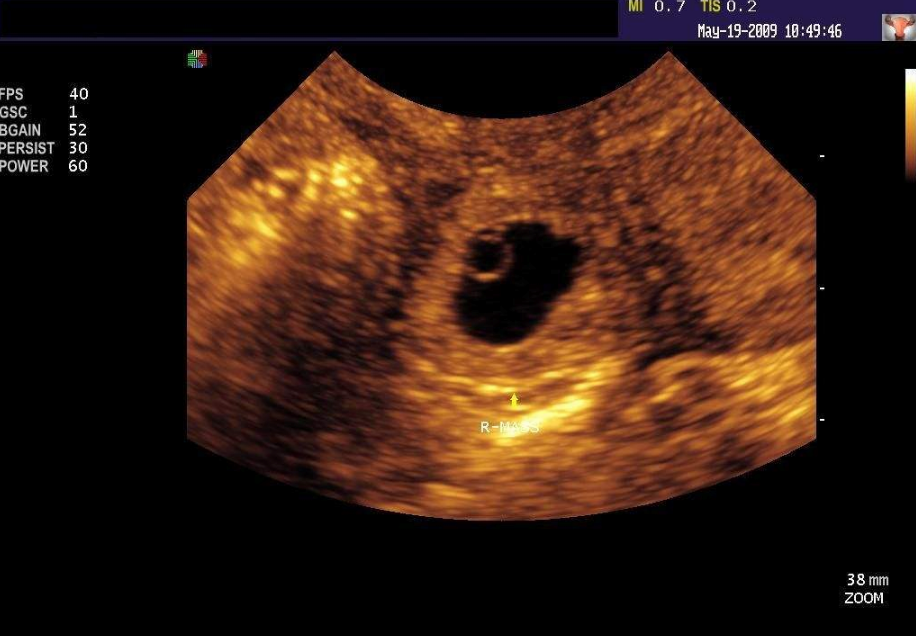

陰道或腹部超聲波檢查:

只要在超聲波檢查后,看到子宮內(nèi)有胚囊,就能夠排除子宮外孕的情況,但懷孕初期的胚囊僅1~2公分,若子宮當下有出血集結(jié)成血塊,也可能誤判為胚囊,因此醫(yī)師會特別注意:另外,胚囊通常于懷孕6周(即為排卵受孕后4周)以上,才可以藉由陰道或腹部超聲波看到,所以懷孕時間過短時,可能還看不到胚囊。